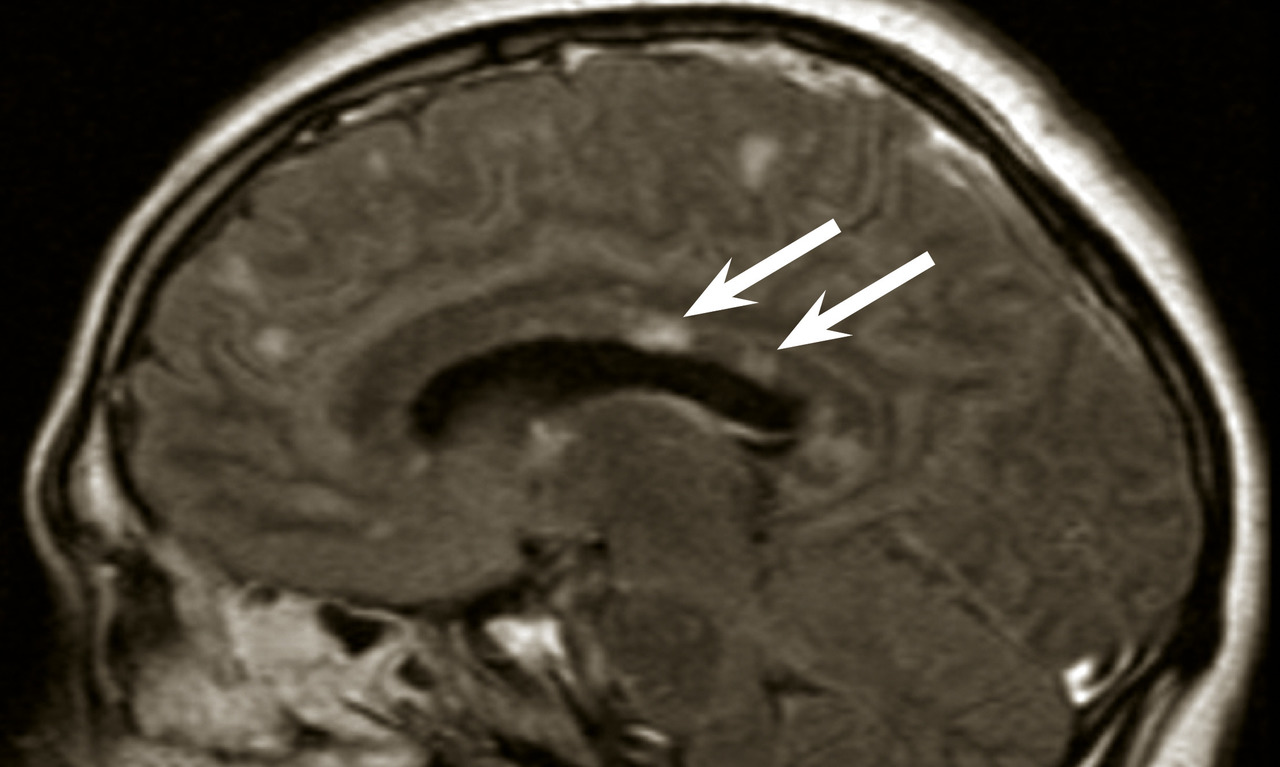

Des critères diagnostiques de la sclérose en plaques ont été établis (tableau 1). Ces critères peuvent permettre le diagnostic de sclérose en plaques dès la première poussée à condition que les critères de dissémination spatiale et temporelle soient remplis. La dissémination spatiale est définie par la présence d’au moins une lésion T2 dans 2 des 4 localisations considérées comme caracté­ristiques de la sclérose en plaques : juxtacorticale, périventriculaire, infratentorielle, au niveau de la moelle épinière (tableau 2 ; fig. 7).

La dissémination temporelle est prouvée par l’apparition d’une lésion en T2 quel que soit le délai par rapport à l’IRM initiale ou par la présence sur l’IRM initiale à la fois de lésions se rehaussant par le gadolinium (signant une lésion récente) et de lésions ne se rehaussant pas (tableau 3). Cette deuxième possibilité évite d’attendre la deuxième IRM pour poser le diagnostic de sclérose en plaques chez certains patients avec un syndrome clinique isolé (ou premier événement démyélinisant). La réalisation d’une seconde IRM est nécessaire pour confirmer une dissémination temporelle chez les patients ne remplissant pas ce critère sur l’IRM initiale. L’alternative permettant de suppléer le critère de dissémination temporelle, chez les patients n’ayant pas sur l’IRM initiale à la fois des lésions prenant le gadolinium et d’autres pas, est que l’analyse du liquide cérébrospinal révèle des bandes oligoclonales.